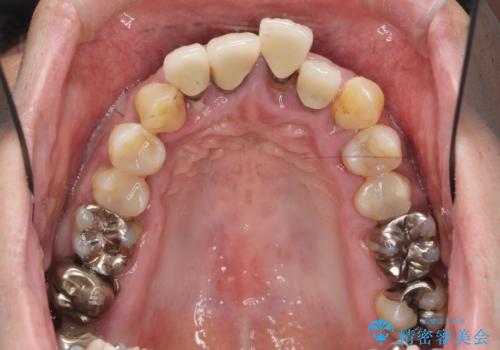

インプラント・ブリッジ補綴を含む、歯周病全顎治療

長期間にわたる治療後、歯に対する意識も大きく変わりプラークコントロールも非常に良くなりました。

数ヶ月に一度のチェックをしっかりと行い、ブリッジ・インプラントが長期間使用できるようメンテンスを行っていきます。